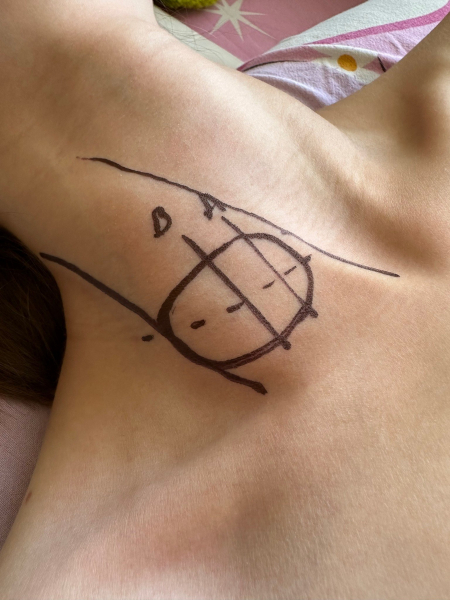

«Команда наших хірургів-онкологів та лікарів-анестезіологів уважно вивчила КТ-зображення та обговорила хірургічну тактику. За годину до операції під УЗД-навігацією розмітили основні анатомічні орієнтири, що значно полегшило роботу в операційній. Положення пацієнтки та методику анестезії узгодили з анестезіологом, а всі інструменти підготували з урахуванням можливих ускладнень.